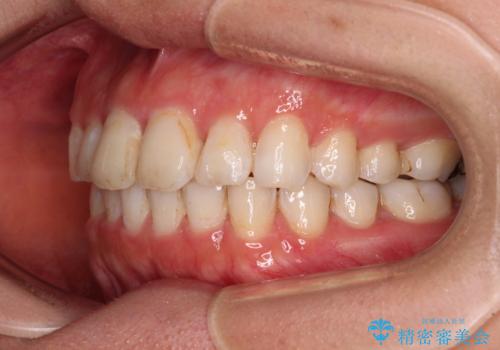

前歯の捻れを改善 インビザラインによる矯正治療

- 前歯の翼状捻転を気にして来院された患者様です。

全体的に叢生は軽度であったため、インビザラインにて矯正治療を行うこととしました。

前歯の幅の大きさも気になっていたため、IPRにより叢生を解消するとともに、歯の大きさも改善しました。